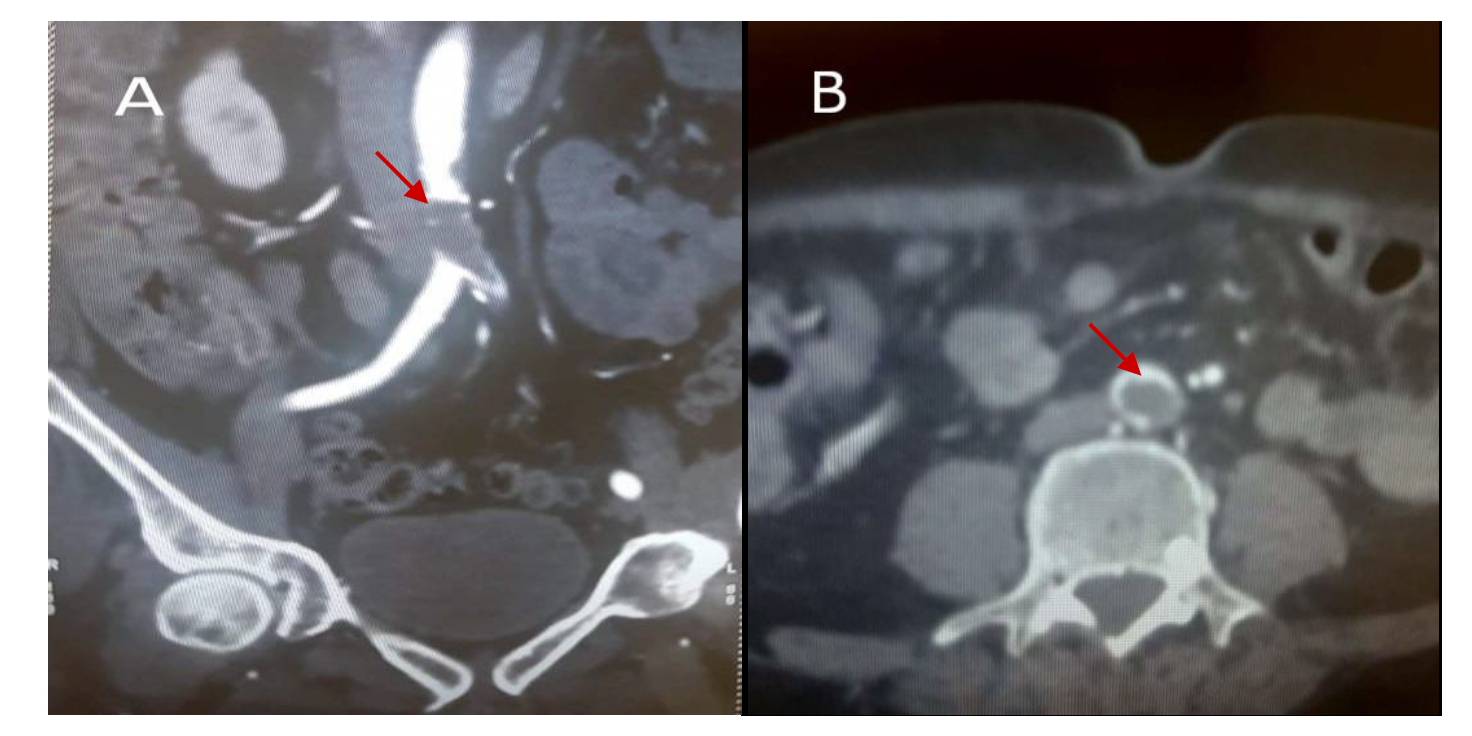

Anatomic location of thrombosis was found on the lower limb in 21 patients (84%) and 4 (16%) presented with upper limb ischemia, with femoral (48%) and brachial (8%) arteries being the most affected. Aortic thrombus was revealed in 7 cases (Figure 1).

All patients required urgent operative intervention. Thrombectomy was performed in 24 patients (96%) and only 1 patient had peripheral vascular bypass. A retrograde transfemoral and popliteal thrombectomy were performed, respectively, in 15 and 6 patients with acute lower limb ischemia. Distal arteries were approached selectively in only 1 patient. Brachial and radial thrombectomy were performed in 4 patients. None of the patients needed fasciotomy. Limb salvage was obtained for all patients except one. Surgical features and anatomic location of the occlusion are summarized in Table 2. Histological examination showed a widely ulcerated endothelial lining with formation of an obliterating thrombosis (Figure 2).